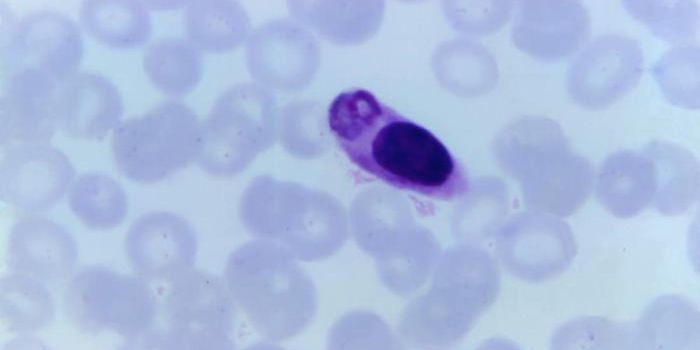

OCT 12, 2020Genetics & GenomicsMosquitoes can transmit the malaria-causing Plasmodium parasite to humans. Malaria was estimated to have caused the deat ...